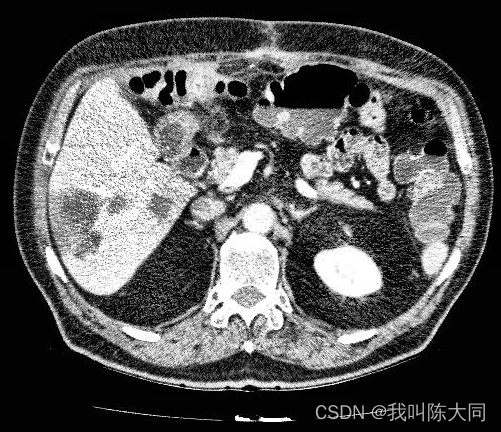

一图为一肝脏CT图像切片可视化结果,已经过预处理转化为灰度图像,组织与器官之间的分界线比较模糊。